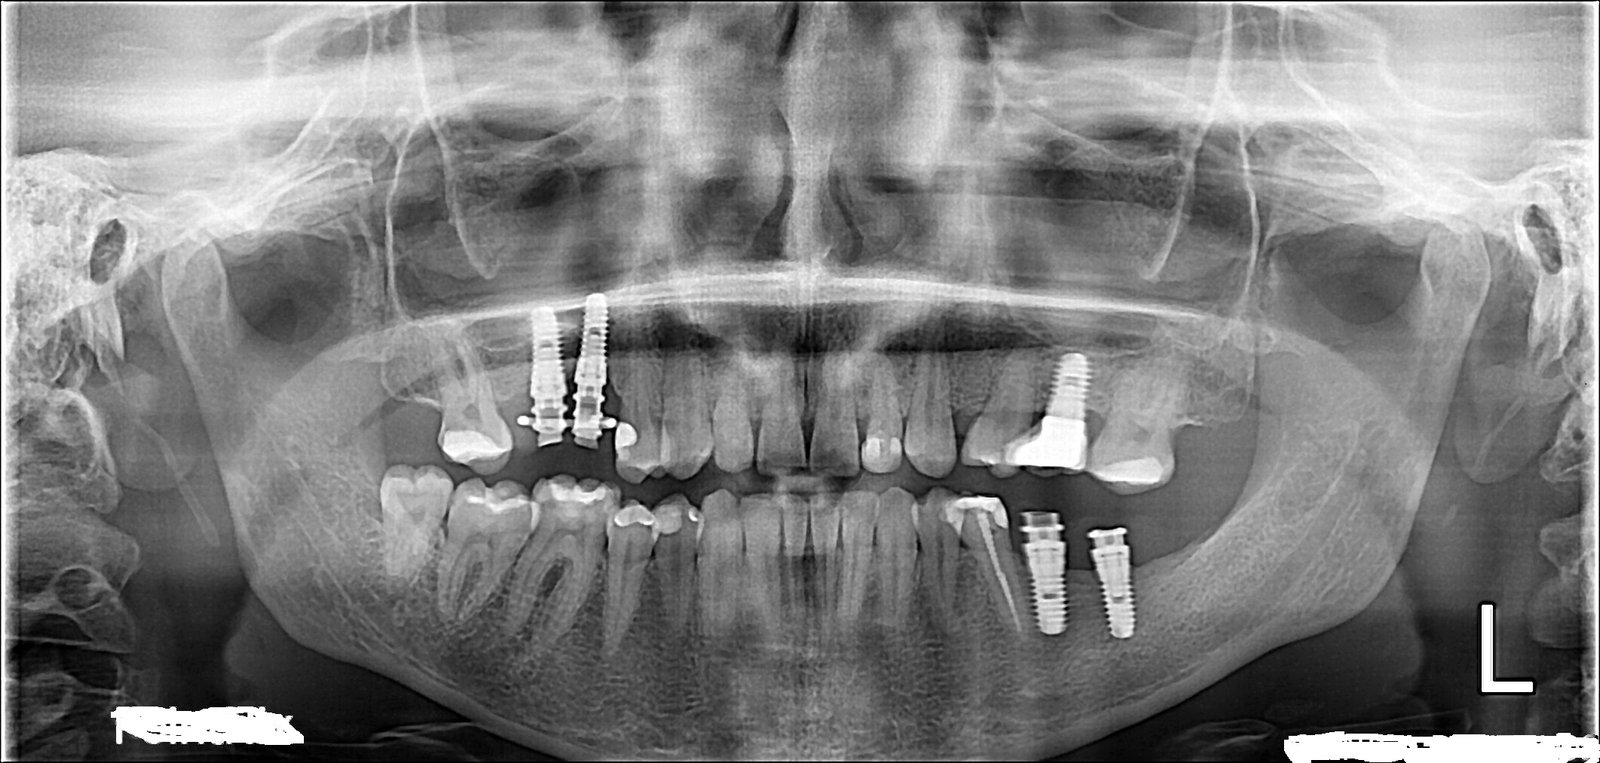

Buenas, esta paciente acude a nuestra consulta porque quiere rehabilitarse los implantes del primer y cuarto cuadrante. Viene desde Idental, porque las coronas que le colocaron (provisionales de resina) se [...]

Necesito saber el tipo de implante que tiene este paciente en piezas 26,27